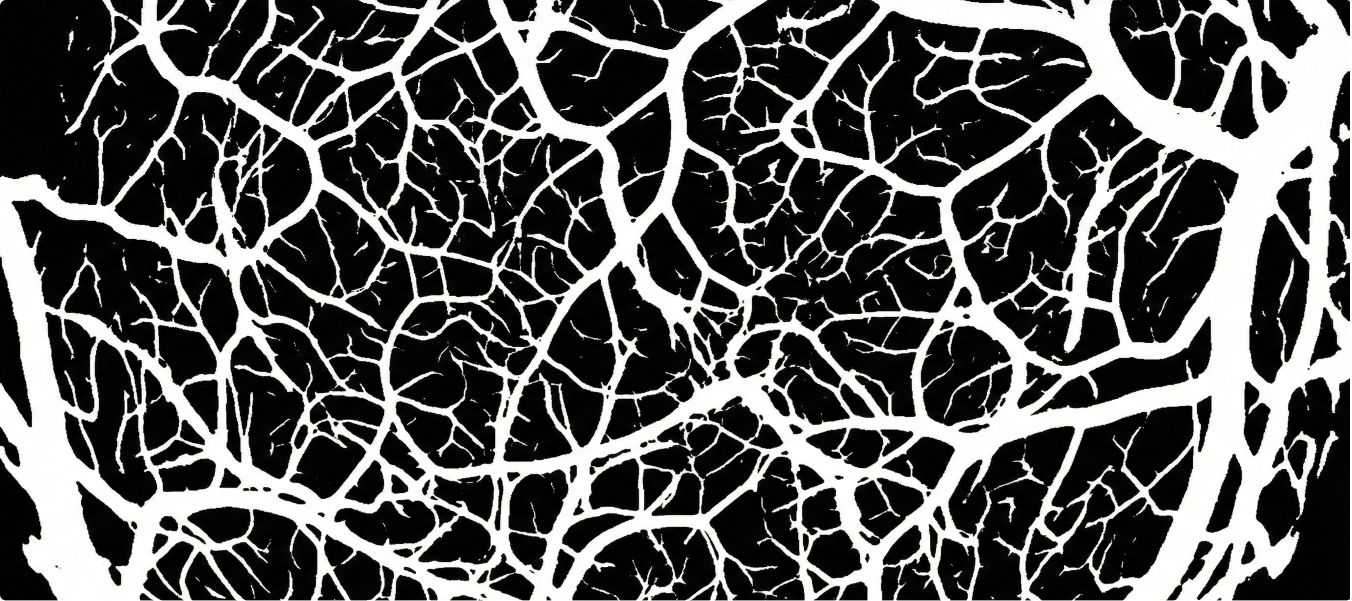

Mapping vasculature in microscopy images required highly detailed semantic annotations. The challenge was balancing speed with precision for thousands of complex images.

• Used semantic 2D annotation for vessel structure mapping.

• Maintained annotation precision with iterative quality checks.

• Delivered large-scale dataset annotation.

• Annotated 15k microscopy images focused on vasculature.

• Each image required an average of 30 minutes, reflecting annotation complexity.

• Delivered results with 95% accuracy, ensuring detailed vascular mapping.